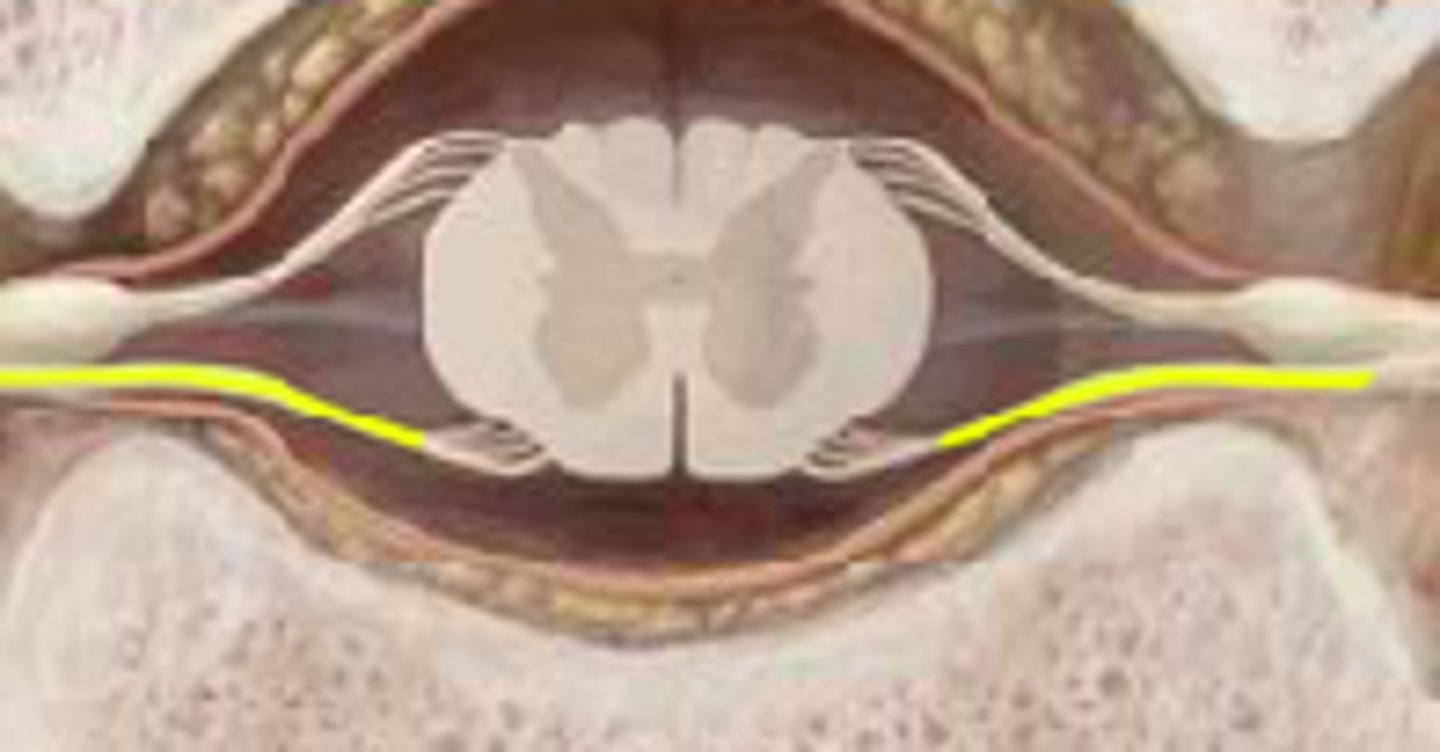

meninges

three protective membranes that surround the brain and spinal cord (AKA: the "maters")

pia mater

thin, delicate inner membrane of the meninges

arachnoid mater

middle layer

dura mater

Outermost layer of the meninges

denticulate ligament

subarachnoid space

contains cerebrospinal fluid

dorsal root ganglion

ventral root